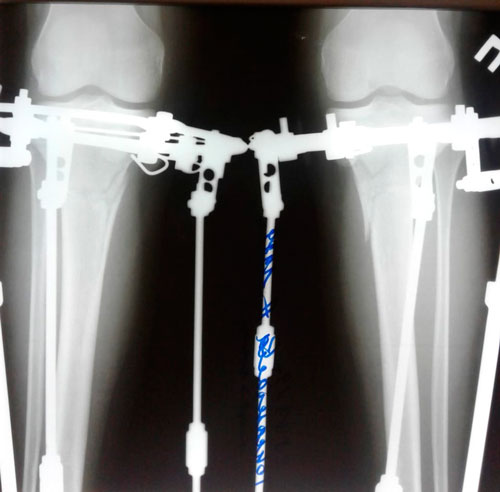

Рентген перед фиксаией!